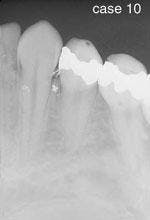

CASE 10

Amalgam tattoo

1. What is the appearance of the amalgam tattoo?

a. blue, black or gray color

b. diffuse border

c. flat

d. any of the above

2. How is the amalgam tattoo most often diagnosed?

a. clinical features

b. histologic features

c. radiographic appearance

d. both a & c

3. What is the recommended treatment for the amalgam tattoo?

a. no treatment necessary

b. surgical removal

c. radiation therapy